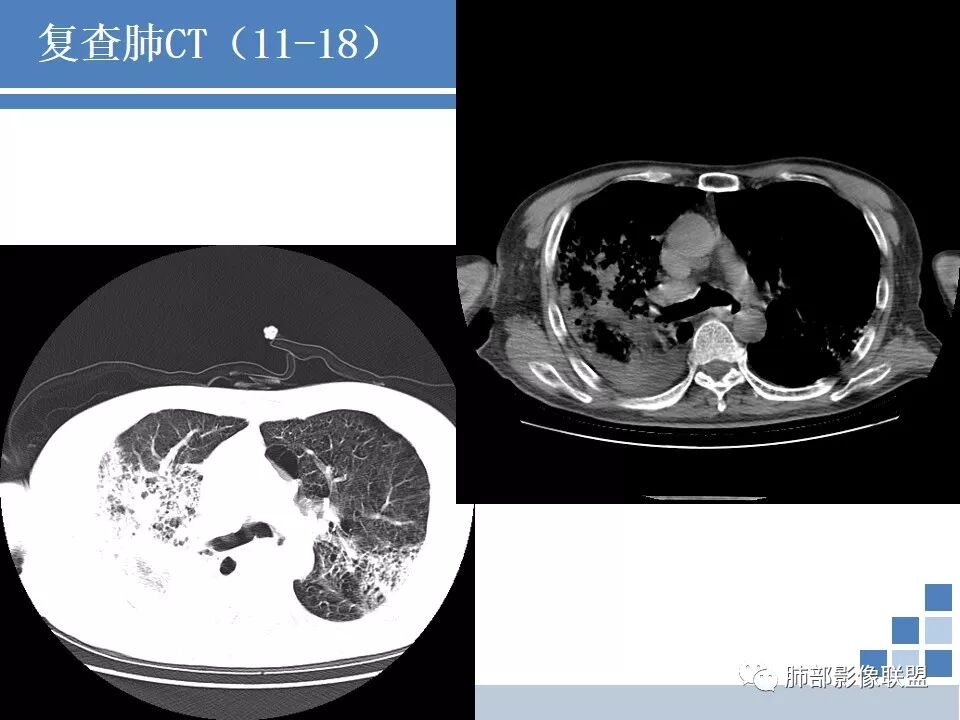

CT:肺气肿肺大泡背景,右上肺磨玻璃及实变影,10天及20天复查影像明显进展至两肺更大范围,伴右侧胸水。

晨读病例:双肺野透光度增强,胸膜下可见肺大泡。右肺上叶病灶三次影像对比病灶增大增多并出现空洞,液平。左肺上叶出现淡片状影,边缘模糊。右侧胸腔积液。考虑感染性病变,结核合并感染。

晨读:右侧胸腔积液,右肺上叶蜂窝状改变加实变,可见空洞形成并见液平,左肺见斑片状及条索状高密度影,左肺下叶呈蜂窝状改变,双肺气肿及肺大泡,考虑感染性病变,不除外结核。

晨读:老年人,咳嗽、咳痰伴发热1周。中性比、白介素6、血沉、CRP、PCT高,低氧血症,结核伽马干扰素阳性,肿标多项阳性。广谱抗生素治疗无效。CT:刀鞘样气管,肺气肿肺大泡背景,右上、下肺大片实变影伴蜂窝,进展快,沿胸膜下分布,有重力分布趋势,胸膜阻隔,10天及20天影像快速进展至两肺更大范围,伴右侧胸水,左上肺也出现病灶。常规考虑:感染性病变,结核?低蛋白明显,奴卡不除外。鉴别:肺炎型肺Ca。